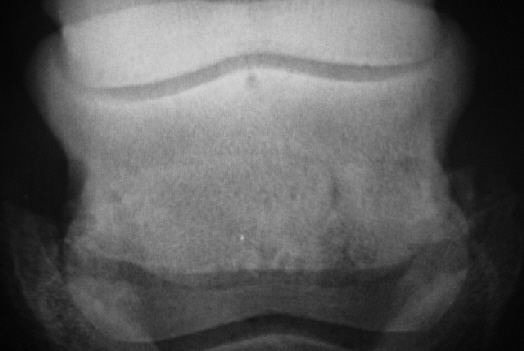

Strahlbeinfrakturen sind relativ selten und dürfen nicht mit Artefakten durch Überlagerung der Strahlfurchen verwechselt werden.

Dies ist das Beispiel eines Strahlbeines, das an den seitlichen Bandansätzen (B) seine normale Kontur verloren hat und eine Fraktur (F) aufweist -  Kategorie IV bzw. Grad 4.

Weitere Beispiele für Strahlbeinfrakturen. (Zum vergrößern und Einsicht der Kommentare anklicken)